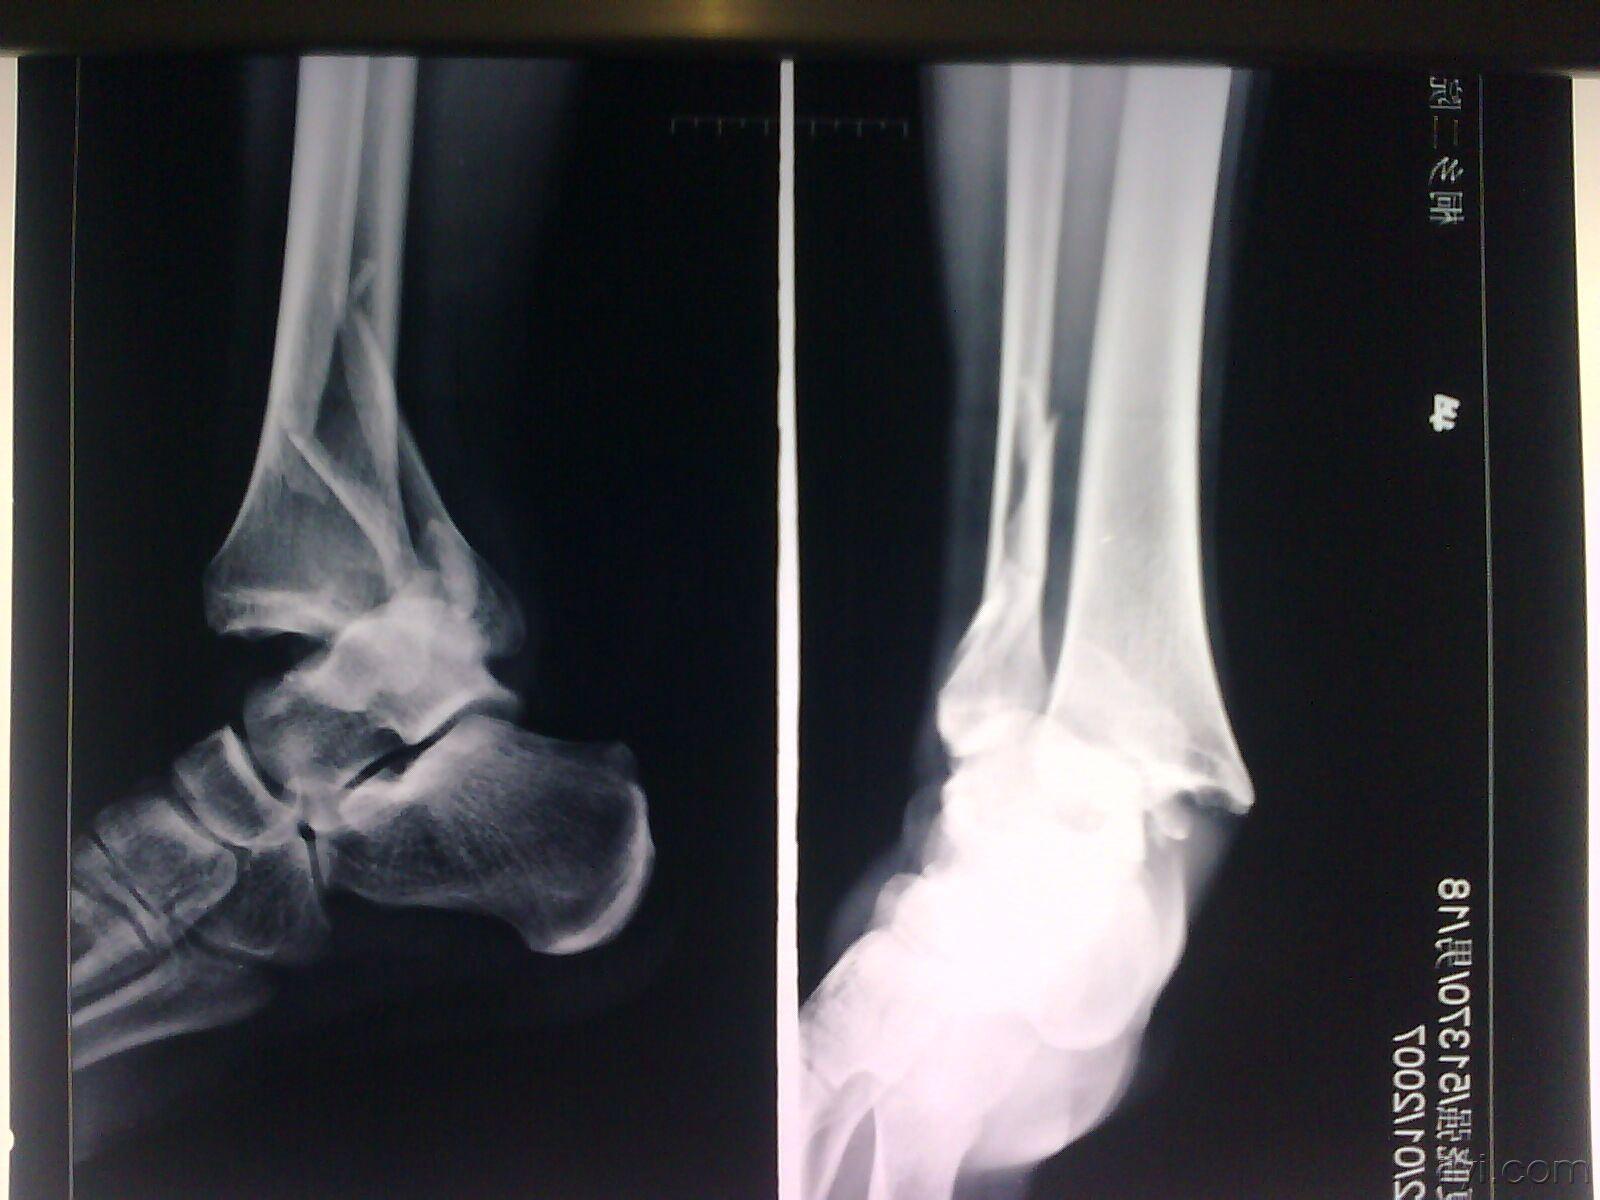

正位显示外踝骨折移位,造成踝关节不稳

侧位显示外踝骨折移位,短缩

一例外踝骨折合并踝关节脱位 [精华]